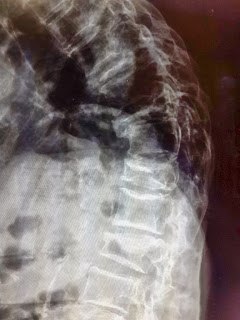

ภาพของผู้ป่วยที่มีหลังโก่งเนื่องจากมีการยุบตัวของกระดูกสันหลัง

นอกจากหลังโก่ง ผู้ป่วยยังมีอาการปวดหลัง ร่วมกับอาการปวดร้าวลงขา ลงน่องและชาบริเวณหลังเท้าร่วมด้วย

ภาพรังสีแสดงการยุบของกระดูกสันหลังหลายระดับ วิธีการดู คือ จะสังเกตจากความสูงของกระดูกสันหลังเทียบกันในแต่ละระดับ จะพบว่าส่วนของกระดูกสันหลังที่ยุบลงนั้นจะมีความสูง

ของกระดูกสันหลังลดลงเมื่อเทียบกับกระดูกสันหลังที่อยู่ติดกัน